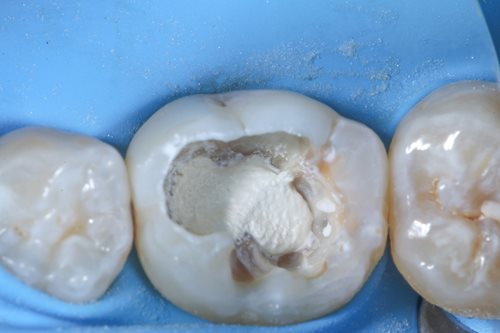

After complete removal of the secondary caries, a partial pulpotomy of the infected but still viable dental nerve was carried out by creating an access cavity with a bur in order to gain access to the mesial pulp horn. To open the mesial pulp horn, Dr. Benjamin used a new sterile instrument to minimize the risks of infection. This was followed by a millimeter accurate excision of the pulp horn, making sure that the pulp horn is removed evenly to create a levelled surface area for the Komet BioRepair putty filling material that is applied later.

Dr. Benjamin then removed any infected debris from the treatment area by constantly rinsing the pulp horn with sodium hypochlorite for disinfection. To prepare the sealing process, he precisely etched the tooth enamel with an etching gel to ensure that the filling material will hold better.